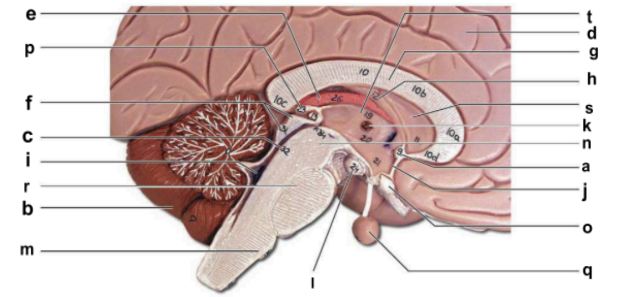

Identify the structure labeled “a” in the image.

anterior commissure

Identify the structure labeled “b” in the image.

cerebellum

Identify the structure labeled “c” in the image.

cerebral aqueduct

Identify the structure labeled “d” in the image.

cerebral hemisphere

Identify the structure labeled “e” in the image.

choroid plexus

Identify the structure labeled “f” in the image.

corpora quadrigemina

Identify the structure labeled “g” in the image.

corpos callosum

Identify the structure labeled “h” in the image.

fornix

Identify the structure labeled “i” in the image.

fourth ventricle

Identify the structure labeled “j” in the image.

hypothalamus

Identify the structure labeled “k” in the image.

interthalamic adhesion

Identify the structure labeled “l” in the image.

mammilary body

Identify the structure labeled “m” in the image.

medulla oblongata

Identify the structure labeled “n” in the image.

midbrain

Identify the structure labeled “o” in the image.

optic chiasma

Identify the structure labeled “p” in the image.

pineal gland

Identify the structure labeled “q” in the image.

pituitary gland

Identify the structure labeled “r” in the image.

pons

Identify the structure labeled “s” in the image.

septum pellucidum

Identify the structure labeled “t” in the image.

thalamus